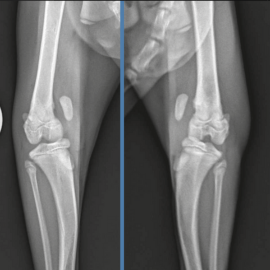

Tratamiento simultáneo de rotura del ligamento cruzado anterior y luxación medial de rótula en la especie felina.